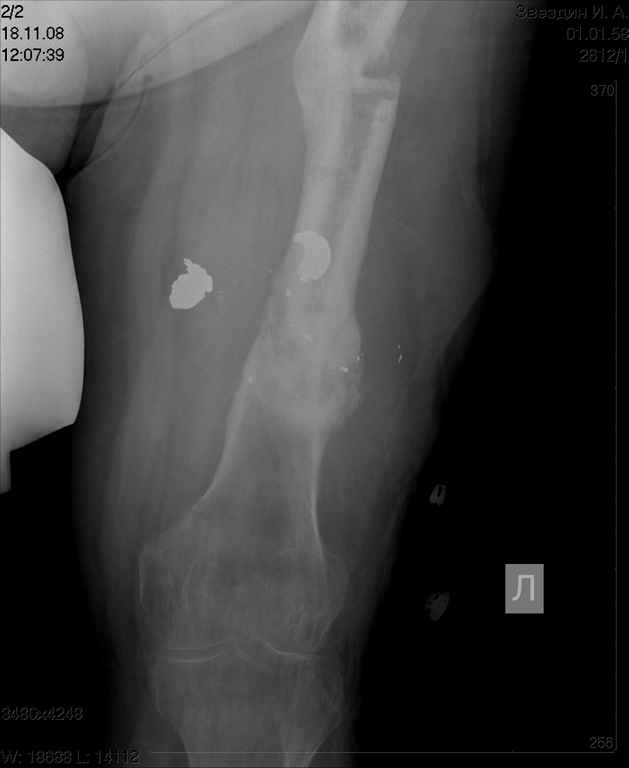

пациент имеет ложный сустав бедра после огнестрельного перелома и длительного лечения Пациент: 48л. ****** (ВРАЧ!) Инвалид 2 группы 3 степени Не работает Жалобы пациента: на невозможность полной нагрузки на левую нижнюю конечность, боли в левом бедре при движениях, в покое, патологическую подвижность в средней трети левого бедра, деформацию и укорочение конечности. Анамнез заболевания. : пациент получил открытый многооскольчатый огнестрельный перелом средней трети левой бедренной кости 24.12.2005г.. В экстренном порядке выполнялась хирургическая обработка раны левого бедра, наложение спице-стержневого аппарата внешней фиксации на левое бедро с вынужденным укорочением сегмента ввиду разрушения и отсутствия костных фрагментов. В послеоперационном периоде рана заживала вторичным натяжением удовлетворительно,без нагноения, выполнялась аутодермопластика дефекта кожи. Фиксация в спицестержневом аппарате в течение 5 месяцев. Правильной репозиции не удалось достигнуть. 24.5.06г. пациент в госпитале Самарского военно-медицинского института повторно прооперирован с установкой спице-стержневого аппарата на бедро и проведением остеотомии в в\3 бедра. Фиксация в аппарате в течение 19 месяцев. Ходил с дозированной нагрузкой на ногу. После снятия аппарата при увеличении нагрузки появилась варусная деформация бедра в зоне остеотомии, признаки образования тугого гипертрофического ложного сустава н\3 бедра. Анамнез жизни. Пациент аллергии на лекарственные препараты не отмечает. Туберкулез, вирусный гепатит, венерическую патологию отрицает. Гемотрансфузии были. Из перенесенных заболеваний отмечает калькулезный холецистит, оперирован в 2006 году – холецистэктомия, осложнившаяся перивезикулярным инфильтратом. Оперирован повторно. – ревизия, дренирование бр.полости. Аппендэктомия в 1993 году. прошу обсудить возможность восстановительного лечения, ПАЦИЕНТ НАСТОЙЧИВО ОТКАЗЫВАЕТСЯ ОТ АППАРАТЕ ВНЕШНЕЙ ФИКСАЦИИ, ИМЕЕТ БОЛЬШОЕ ЖЕЛАНИЕ ДОНОМОМЕНТНОГО ОСТЕОСИНТЕЗА С УСТРАНЕНИЕМ ДЕФОРМАЦИИ И УДЛИНЕНИЯ..

посылаю снимки отдельно

такое ощущение, что пациента на предыдущих этапах лечили только по снимкам нижней трети бедра в прямой проекции.